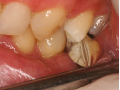

Flowable Injection Technique – kompozytowa alternatywa dla…

Technika Injection Flowable i technika stempla. Odbudowa…